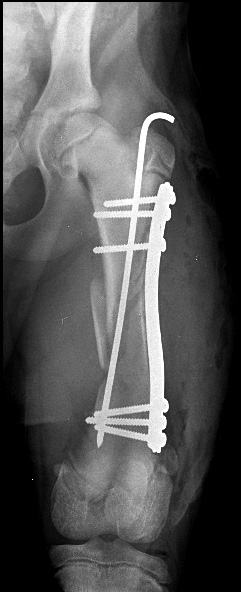

Sur les deux études précédemment citées, seule une complication majeure dans la seconde étude 11 a été observée, sur un total de 41 chiens. Il s’agissait d’un pliage de la plaque d’ostéosynthèse au niveau du foyer de fracture sur un jeune beauceron de 4 mois, 3 jours après la chirurgie. Cette fracture, réopérée à la suite de cet échec avec une plaque DCP pour vis de 2,7 mm et 3 vis dans chaque fragment osseux (donc avec un montage rigide) a cicatrisé légèrement moins vite que les autres (cal complet en 8 semaines). Le résultat final après ablation du matériel d’ostéosynthèse a été jugé excellent.

Il est donc impératif de tenir compte de plusieurs critères avant de choisir le traitement par ostéosynthèse élastique : l’âge de l’animal est bien sûr un critère primordial, mais il doit être corrélé au poids (et donc aux contraintes mécaniques induites par l’appui du membre) ainsi qu’au degré d’activité prévisible du chiot durant la phase de cicatrisation osseuse. Dans certains cas, il peut être préférable d’associer un clou centromédullaire de faible diamètre pour diminuer les contraintes sur la plaque sans trop augmenter la rigidité du montage ou encore d’associer deux plaques VCP « sandwichées ».